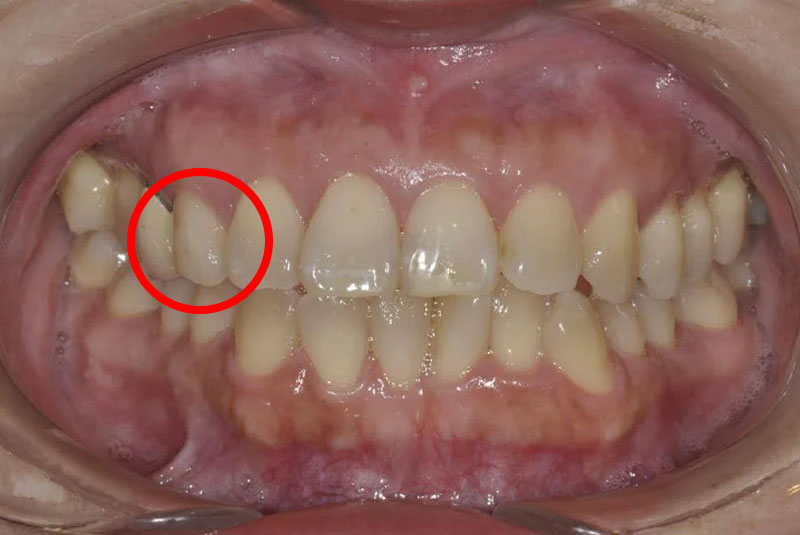

ホワイトニング前・初診時口腔内写真

ウォーキングブリーチ直前